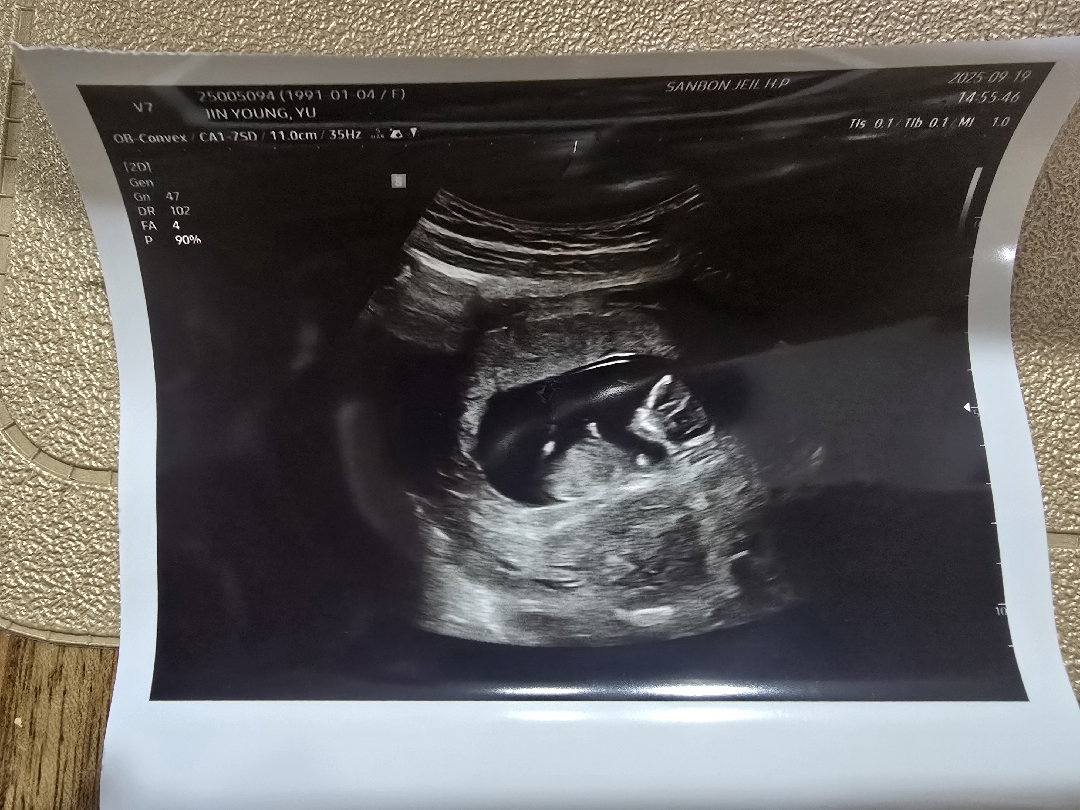

딸?아들? 한번봐주세요!!!

첫째..딸일까요????

아들같아보여요

각도보기에 사진이 애매해용